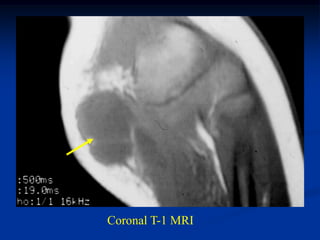

Case #284

Coronal T-1 MRI

49 year male with

well-differentiated

liposarcoma (atypical lipoma)

distal thigh

Sagittal T-1 MRI

Axial T-2 MRI

Case #284 Coronal T-1MRI 49 year male with well-differentiated liposarcoma (atypical lipoma) distal thigh